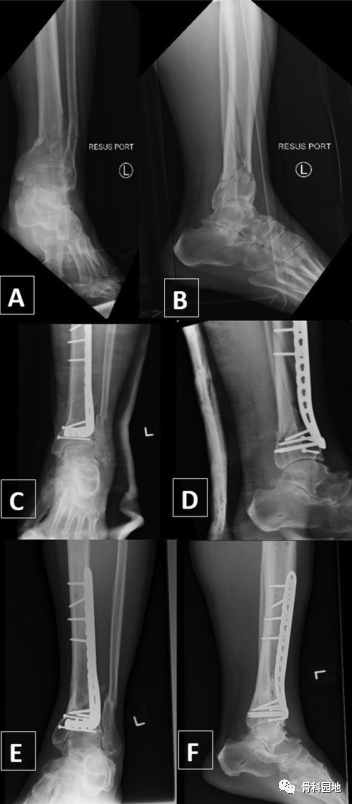

一、没有腓骨固定的情况下使用前外侧胫骨远端钢板固定骨折

二、使用内侧胫骨板和腓骨钢板固定。

三、使用前外侧钢板固定胫骨和腓骨克氏针固定。